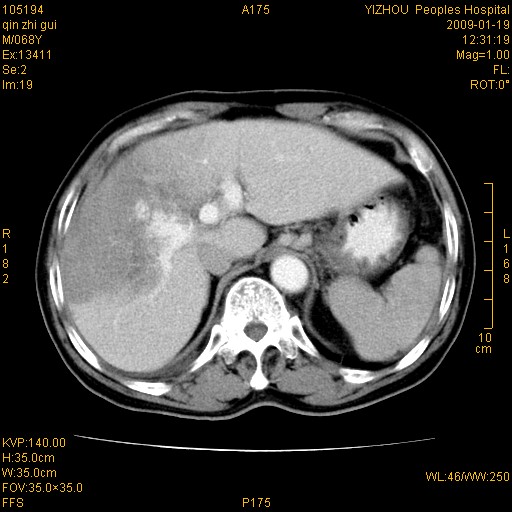

以下是引用随光逐影在2009-1-21 16:11:00的发言:[br]1)考虑肝右叶肝癌并肝静脉及门静脉瘤栓形成。2)肝硬化,少量腹水。3)胆囊炎。4)右侧少量胸腔积液。

病灶外缘凹凸不平,平扫低密度,增强动脉期有强化,门脉早显,静脉期及延期呈延迟强化,结合病史考虑右肝前叶巨块型肝癌可能性大,强化表现不除外胆管细胞癌